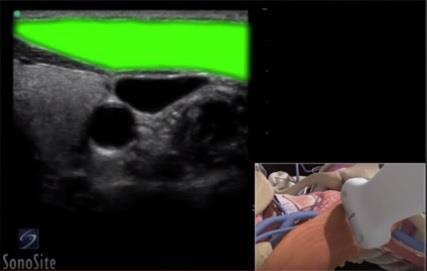

Vascular Sternocleidomastoid Muscle Highlighted Image

Highlighted Area: Sternocleidomastoid Muscle